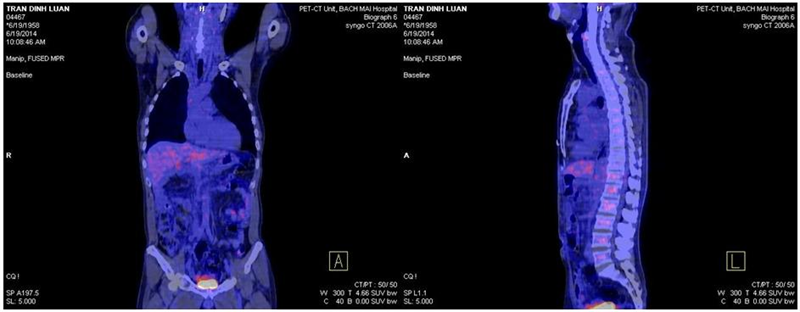

Hình 2: Khối tá tụy đã cắt, hiện tại không thấy tổn thương tái phát, di căn.

Sau 6 chu kỳ hóa chất bổ trợ, chúng tôi đánh giá bệnh nhân đáp ứng tốt với điều trị.